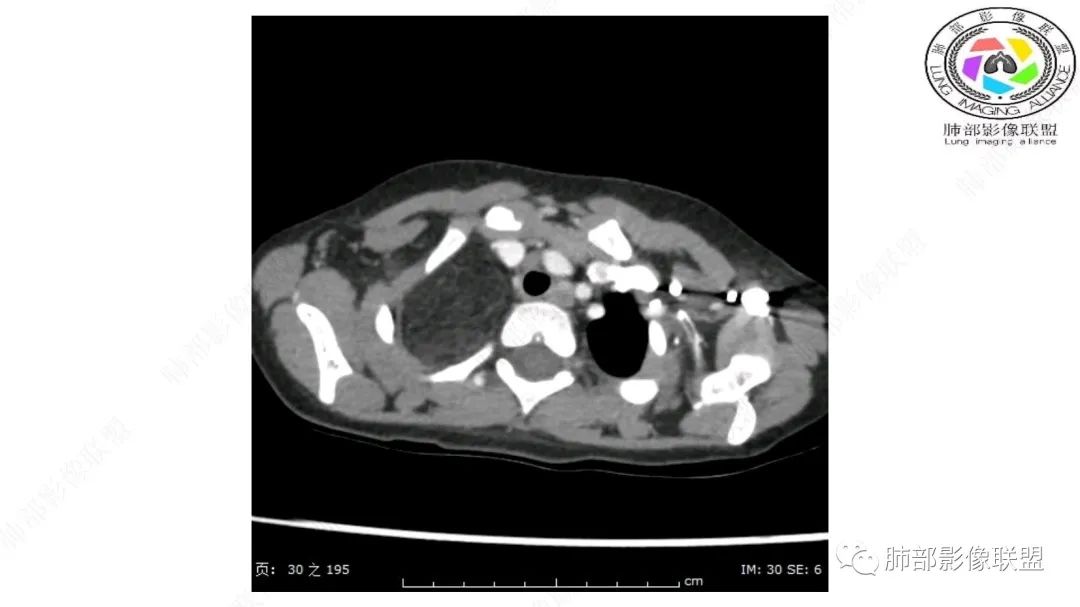

右上纵隔混杂密度肿块,边缘光整,与纵隔分界清,其内多发脂肪密度,增强无明显强化,其内血管穿行,考虑纵隔脂肪母细胞瘤,鉴别畸胎瘤,脂肪肉瘤。

右纵隔团状,密度不均,脂肪密度为主,内可见腺体样组织,类似乳腺,病灶边缘有分叶,与胸腺关系密切,增强后血管穿行。考虑胸腺脂肪瘤(不典型垂乳征),鉴别畸胎瘤。

跨肺门,包绕肺血管分支,邻近肺组织受压肺不张。

可以看到造影剂进入的丛状结构

密度不均,非纯脂肪成分。斑片状密度略高区域有轻度填充式强化。

病灶属于交界区,主体位于肺内,占位效应明显,前方突入胸壁,胸腺受压变形,胸膜显示欠清楚;病灶包绕上叶肺动脉;似乎有体动脉供血。符合肺内的点:包绕上叶肺动脉分支;符合纵隔的点:前方似乎突入胸壁,与胸腺关系比较密切,但是与上腔静脉的关系提示病灶不支持纵隔来源,前纵隔的常规会将上腔静脉受压后移、外移,这是不符合的。

2.肺动脉穿行也许是肺内来源最重要支持点!